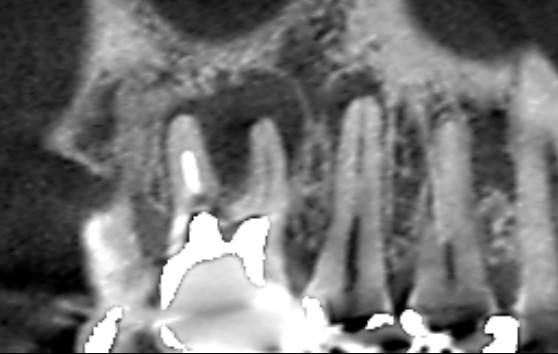

第一大臼歯の精密再根管治療1年後の冠状断のCT画像です。赤い矢印の先が、パーフォレーションリペアをしたところです。赤い矢印の先にあった膿の影が消え歯槽骨が再生しています。